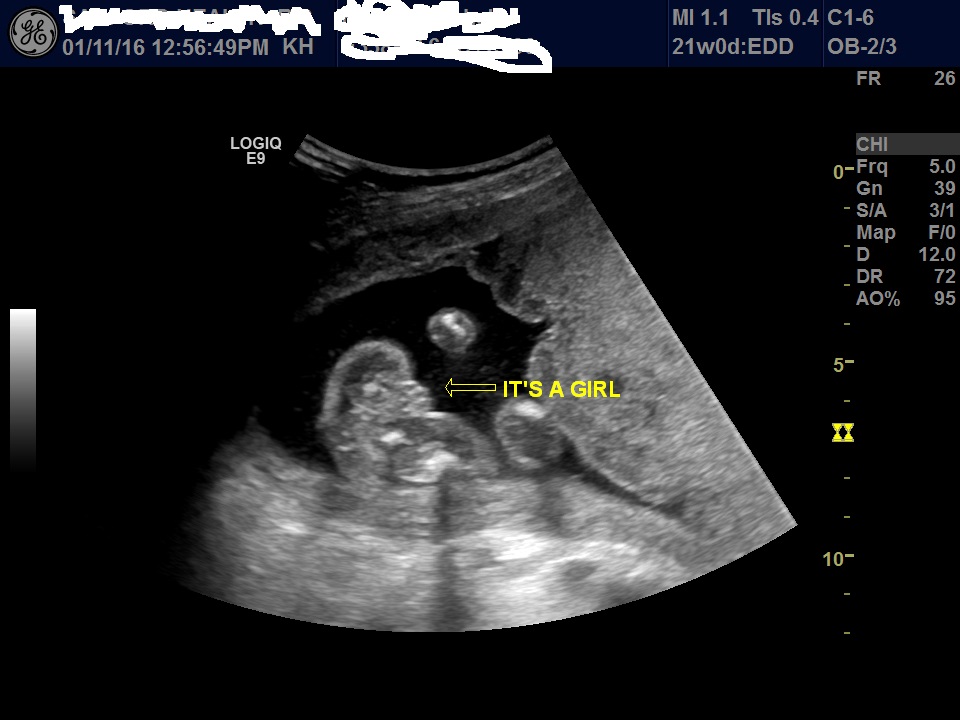

I stupidly went on ingender's site and looked at their ultrasound opposites thread and now I'm not so sure this is really a girl. The one picture looks like it's taken from too far back and could be scrotum and the other one looks like a girl, but I'm not so sure. I have an ultrasound at 24 weeks and 28 weeks so I'll be having the tech double check each time, but right now I'm having doubts! Are these ultrasound pictures good shots of a girl? She was able to tell me right away what the gender was so she didn't really look around too much (even though I did make her double check 3 times...)

Attachment 29402